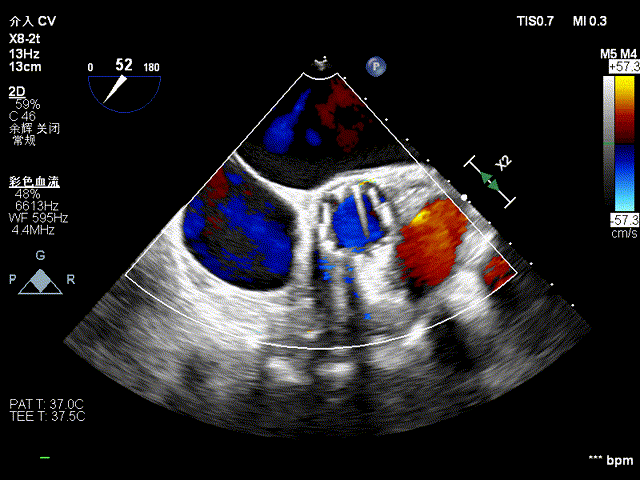

术后食道超声

术后心脏超声示

经心尖主动脉瓣生物瓣置换术后,生物瓣功能未见明显异常,微量心包积液。LVEF:68%。

主动脉瓣位生物瓣,瓣架固定,瓣叶启闭尚可,主动脉瓣位生物瓣前向峰值流速约1.8m/s,平均跨瓣压差约8mmHg,舒张期少量周反流。